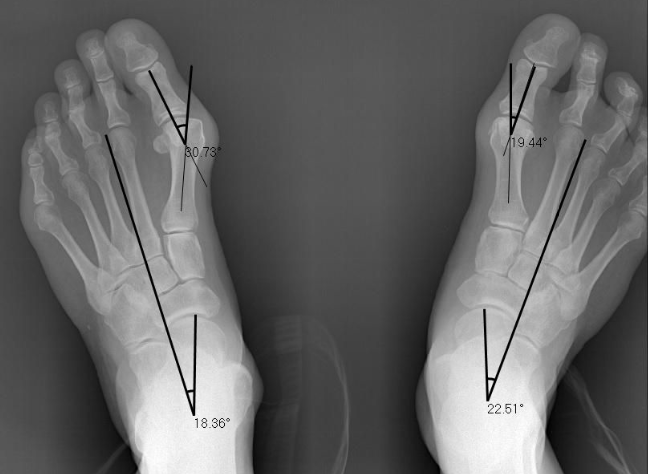

We completed his initial assessment which included an x-ray. This is Grahams initial x-ray. As you can see below his x-ray shows a bunion angle of 30.73 and 19.44 degrees. The ideal angle is 12-15 degrees.

We followed up with another x-ray to measure Grahams results. We manged to get down to 16.92 and 11.28 degrees! In Grahams case he has had a significant improvement! Not only have his bunions straightened, his foot pain has resolved.